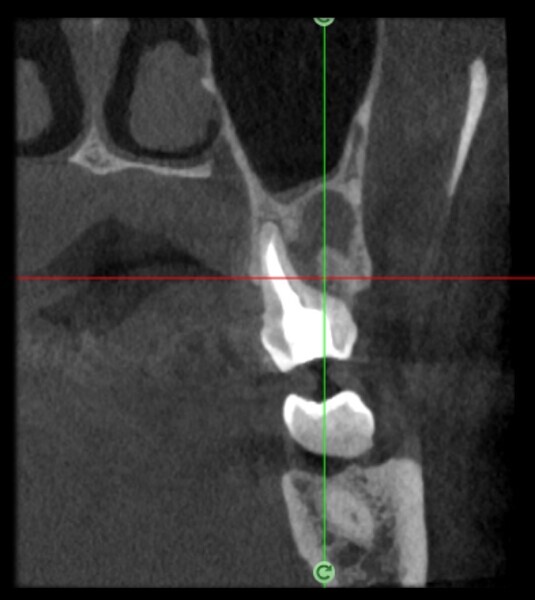

Use of 3D technology in the diagnosis and treatment of endodontic disease